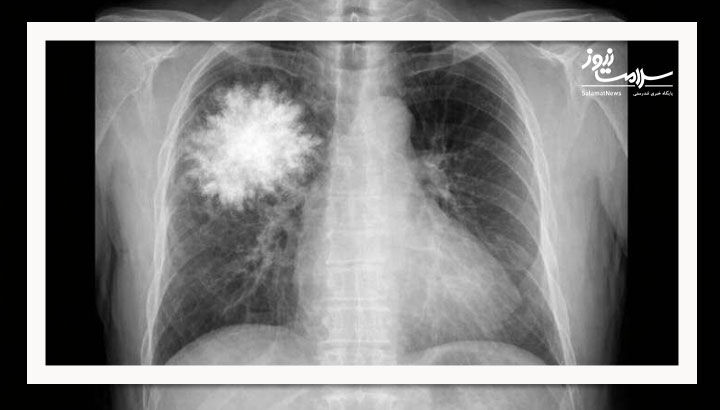

گروه پژوهشی یک قدم فراتر رفت و یک مدل فقط متنی (بدون دسترسی به دادههای بصری) را برای پاسخ به سؤالات مربوط به عکسهای قفسه سینه آموزش داد.

نتیجه شگفتآور بود: این مدل متنی در یک آزمون استاندارد تفسیر عکس قفسه سینه، هم از سامانههای پیشرفته هوش مصنوعی و هم از پزشکان انسانی بهتر عمل کرد.

این یافتهها نشان میدهد که سامانههای ارزیابی فعلی ممکن است بیش از حد به الگوهای متنی تکیه کنند تا درک بصری واقعی.